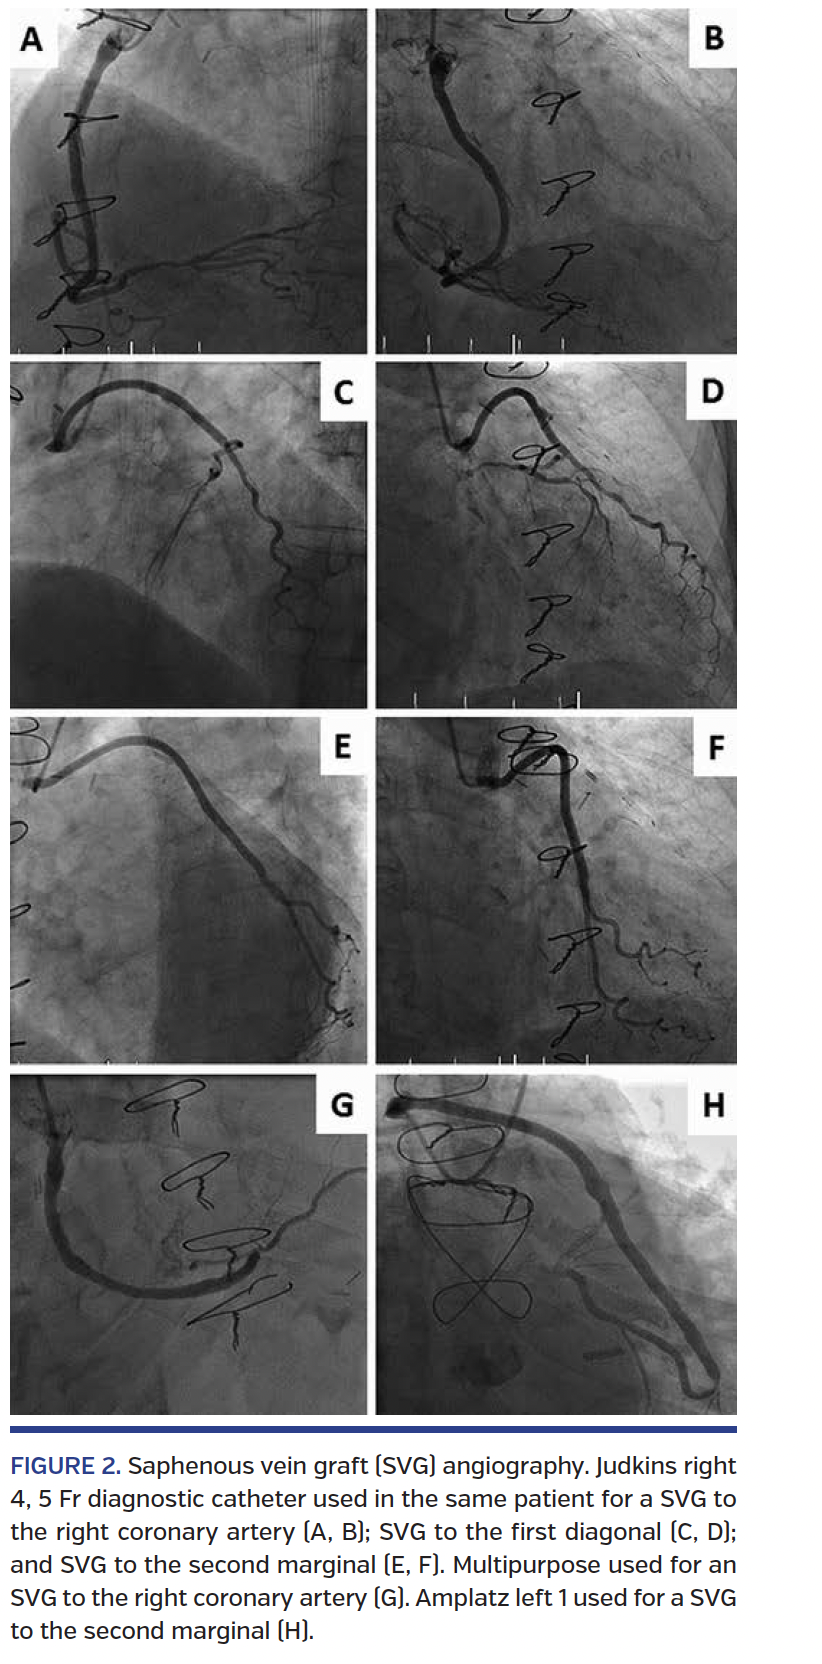

Saphenous vein graft cannulation. For an SVG to the right coronary artery (RCA), after RCA angiography with a JR 4, the same catheter usually reaches the SVG ostium (Figures 2A and 2B). However, after unsuccessful attempts or inability to selectively cannulate the SVG, we prefer to switch to a multipurpose catheter (Figure 2G), as it offers a more coaxial cannulation. If it fails again, then we switch to an Amplatz left (AL) curve 1, 2, or 3 depending on the ascending aorta diameter. If PCI is needed, we prefer a Multipurpose first followed by an AL curve. When the right radial access is initially obtained, first try a Multipurpose or AL curve. If PCI is needed, either a Multipurpose or AL will sit well.

For SVGs to the left coronary system, a JR 4 may allow cannulation of the SVG ostium (Figures 2C-2F). However, if it fails, we prefer to switch to an AL-1 (Figure 2H), AL-2, or AL-3 depending on the ascending aorta diameter followed by a left coronary bypass (LCB) catheter. When the right radial access is used, first try an AL curve, then a Tig or LCB catheter. If PCI is needed, we prefer AL curves since JR or LCB catheters do not provide much support. Notably, when using the right radial approach, a one-size bigger catheter would also be advised, ie, AL-1 from the left radial and AL-2 from the right radial.